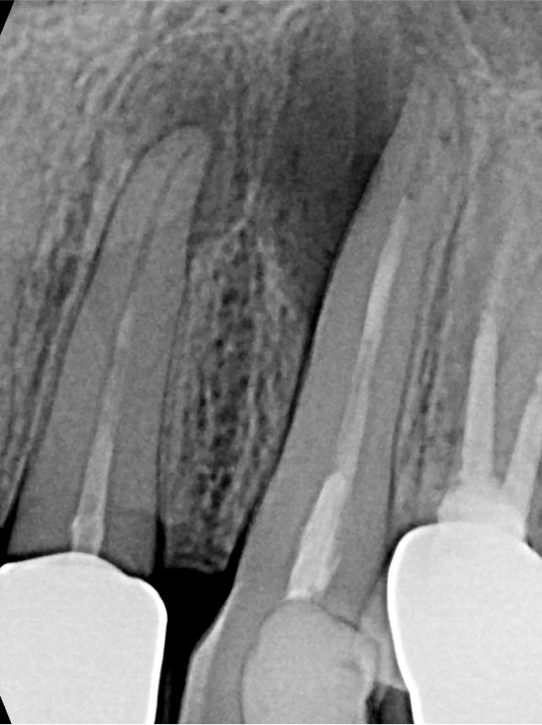

Czy leczenie kanałowe można powtórzyć? Tak, ponowne leczenie endodontyczne (tzw. re-endo) jest możliwe i często konieczne, gdy poprzednie leczenie nie przyniosło oczekiwanych rezultatów lub pojawiły się nowe problemy w danym zębie. W takich sytuacjach precyzja jest jeszcze ważniejsza.

Użycie mikroskopu zabiegowego jest nieocenione, zwłaszcza przy powtórnym leczeniu. Mikroskop pozwala na precyzyjne odnajdywanie dodatkowych kanałów, które mogły zostać pominięte podczas pierwszego leczenia, a także na dokładne opracowanie systemu kanałowego. Dzięki niemu możliwe jest również usuwanie wkładów metalowych czy złamanych narzędzi.

Jednym z wyzwań w leczeniu endodontycznym jest usuwanie złamanych narzędzi z kanałów korzeniowych. To skomplikowana procedura, która wymaga ogromnego doświadczenia i zastosowania mikroskopu, ale w naszym gabinecie podejmujemy się takich wyzwań, aby uratować Twój ząb.

Zarówno ziarniniak okołowierzchołkowy i torbiel zębopochodna uszkadzają struktury okolicznej tkanki kostnej. Podobny proces jeszcze do niedawna był książkowym wskazaniem do interwencji chirurgicznej lub nawet usunięcia zęba. Przy obecnym stanie wiedzy praktycznej wynikającej z doświadczeń pokoleń lekarzy oraz szerokim dostępie do nowoczesnej, specjalistycznej aparatury medycznej, metody terapii stały się mniej inwazyjne, bardziej przewidywalne, mniej radykalne i z założenia prowadzą do zachowania zęba w jamie ustnej.

LECZENIE ENDODONTYCZNE ZE SKOMPLIKOWANĄ ANATOMIĄ ZĘBA